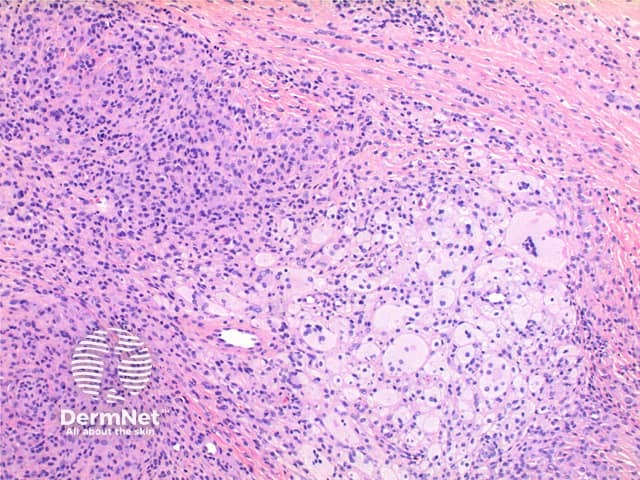

Scanning power view of giant cell tumour of tendon sheath identifies a well circumscribed tumour nodule arising in the deep dermis or subcutis (Figures 1-3). The tumour nodule is comprised of a population of oval cells set in a minor condensed eosinophilic fibrous stroma (Figures 4 and 5). Scattered multinucleated giant cells are present (Figure 6). In most cases small clusters of lipid laden cells can be seen (Figures 7 and 8) .